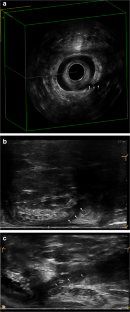

This was a retrospective cohort study of consecutive patients subjected to FiLaC™ at Digestive Disease Center, Bispebjerg University Hospital, Copenhagen, between March 2017 and July 2019. All patients had a one-track fistula not suitable for fistulotomy. All were treated with a draining seton for at least 8 weeks prior to laser closure. Fistulas were ablated with a 360-degree emitting 12-watt 1470 nm laser probe. The inner fistula opening was closed with absorbable suture. All patients were followed with clinical examination including MRI or EAUS 1 year after the procedure.